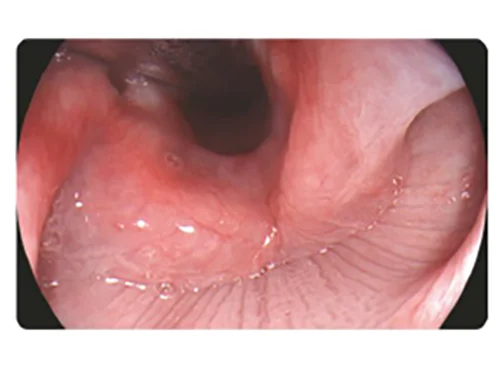

DSI: Двухцветная визуализация

Слабая проницаемость и сильное рассеивание фиолетового и зеленого света позволяет хорошо визуализировать морфологию кровеносных сосудов слизистой оболочки . Кроме того, свет в этих двух диапазонах легче всего поглощается гемоглобином, что уменьшает отражение и рассеивание и повышает контрастность между кровеносными сосудами и окружающей тканью.

Применение

- Точное обследование пораженных участков слизистой.

- Определение инфильтрации и границы пораженного участка.

- Выявление и классификация опухолевых образований.

Белый свет

DSI